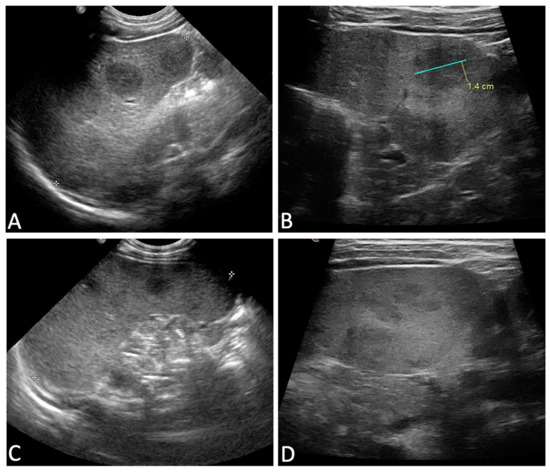

In terms of clinical presentation, as shown in Table 1, all but one child (93.8%) had a fever, with a median body temperature of 39.7 °C. Splenomegaly occurred in 15 (93.8%) children, with a median spleen diameter of 9.3 cm (range 7.5–15.4). In addition, 11 out of 15 children (73.3%) had hypoechogenic areolae in the spleen as a distinctive ultrasound abnormality (Figure 2). Such lesions, characterized by a less defined echotexture, were better evaluated using high-frequency linear probes, which offer increased detection sensitivity in these cases. None of our patients had cutaneous lesions caused by Leishmania.

Figure 2.

Variable ultrasonographic presentation of splenic lesions in VL. (A,B): large lesions with more clearly defined borders when compared to the surrounding healthy parenchyma. (C,D): small lesions that appear mildly hypoechoic in comparison to the surrounding parenchyma. (A,C) were taken with a convex probe, which is useful to better identify spleen dimensions and bigger lesions. (B,D) were taken with high-frequency linear probes, which are crucial, especially in the case of smaller lesions (D) that have a less defined echotexture, for which these probes offer increased detection sensitivity.

About two-thirds of our patients showed focal subcentrimetric hypoechoic splenic lesions, which have been shown to be frequent during ultrasound examinations in pediatric VL [14,31]; this ultrasound signature can be considered a useful diagnostic tool to suspect L. infantum infection in children. However, in the presence of these splenic abnormalities, alternative differential diagnoses, such as infectious, lymphoproliferative, or congenital conditions, should be investigated. Importantly, the presence of splenic abnormalities does not indicate a poor prognosis for patients with VL [32].

Regarding hematological alterations, hemoglobin levels normalized relatively quickly, with nearly half of the patients who did not receive blood transfusions showing an improvement at the time of discharge and complete normalization within a few months after the therapy, which is consistent with findings from other studies [29,30]. In contrast, as previously reported, the resolution of the ultrasonographic findings required longer times, and the disappearance of the hypoechoic splenic lesions proved to be a slower process than the resolution of splenomegaly [31]. Nevertheless, it is challenging to compare our data with other groups due to the small size of our cohort, variability in the timing of follow-up ultrasound scans, and limited available data on post-hospitalization follow-up [31,33]. According to a recent narrative review on ultrasonography findings in VL, splenomegaly can persist in a minority of patients for up to 8–10 months following treatment, while the clearance of splenic nodules has been reported to occur within 2–4 weeks or a few months after treatment [33].